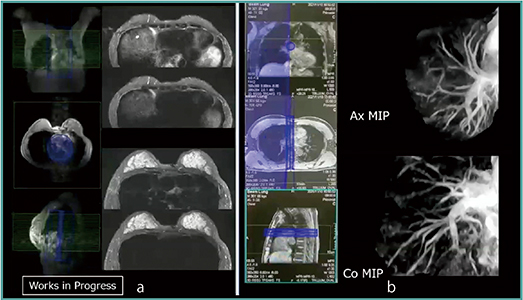

また,すでに頭部で製品化されている選択的2D Excitation(Beam)技術の躯幹部への応用を進めている(W.I.P.)。Beam技術では,BeamSatパルスを用いて選択的に血管を励起し,任意に血管を描出することが可能で,腹部MRAや胸部MRAでも末梢まで血管を明瞭に描出することができる。Beam技術はさらなる応用が可能で,例えばBeamSatパルスを心臓部分に印加して心臓からの信号を抑制することで,心臓からのアーチファクトを軽減することができる(図2 a)。また,肺へも応用することができる。肺野に長方形にIRパルスを与えて静脈信号を消した上で,肺動脈にBeamSatパルスを印加すると,肺動脈を経時的に観察することができる(図2 b)。

図2 Beam技術の応用:心臓(a),肺動脈(b)